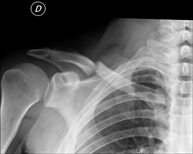

- RX Clavículas

Técnica mediante la cual, utilizando rayos X, se obtienen imágenes de las clavículas para su estudio.